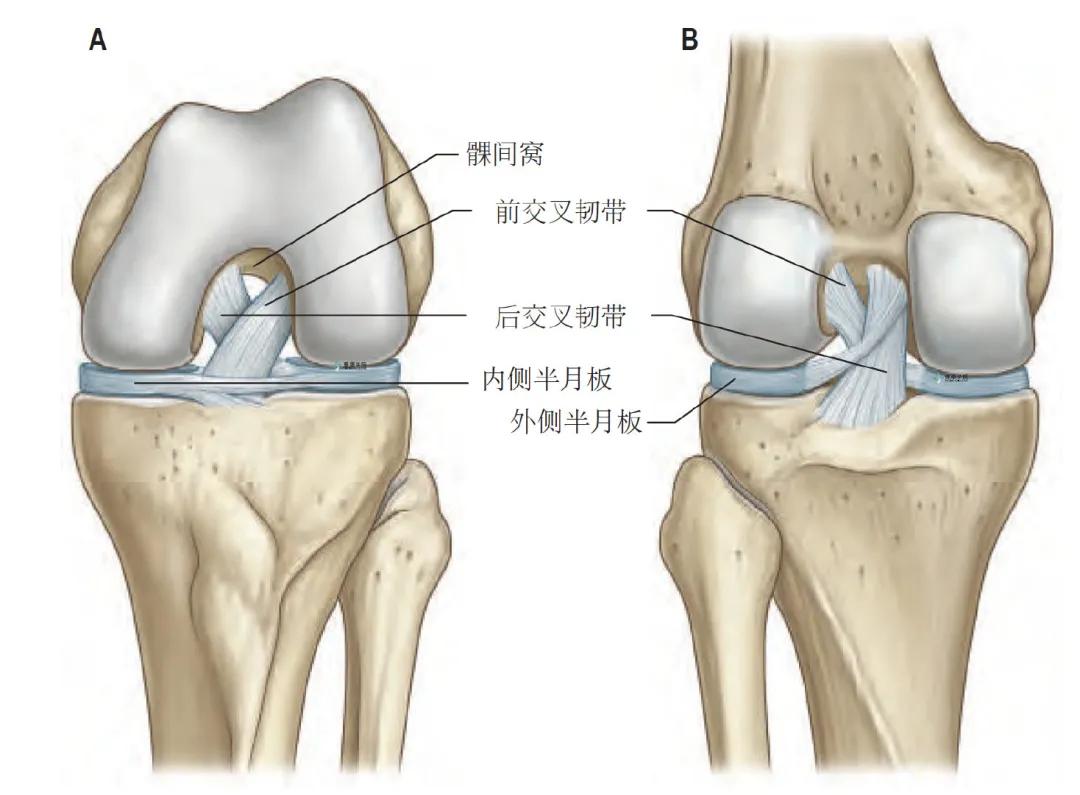

交叉韧带

交叉韧带,因两条韧带彼此交叉而得名,为有丰富神经支配的结构,其交叉点位于关节中部稍偏后,根据胫骨止点位置而命名“前后”。韧带被滑膜包绕,但滑膜从后交叉韧带向后反折,与附近关节囊相连;髁间后部的纤维囊缺少滑膜覆盖。

前交叉韧带起自胫骨髁间前区,附着于内侧髁间结节前方稍外侧,部分与外侧半月板前角融合。前交叉韧带向后外螺旋上行,呈扇形散升附着于股骨外侧髁的后内侧面。

后交叉韧带比前交叉韧带更厚、更强韧。附着于股骨内侧髁的外侧面,常延伸至髁间窝顶的前部,此处的附着点呈前后方向, 其纤维靠近关节面。后交叉韧带向后下方走行, 附着于胫骨髁间后区和邻近的胫骨后方的凹陷处。这使后交叉韧带呈扇形展开,其纤维走行方向不同,分为前外侧束和后内侧束。